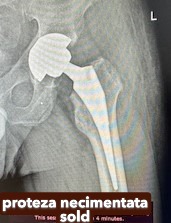

Endoprotezele de șold pot fi:

• cimentate,

• necimentate,

• hibride.

Endoprotezele totale cimentate se implantează la persoanele vârstnice, cu osteoporoză, la care articulația nu poate menține proteza fixată prin presiune și care necesită cimentarea componentelor.

Galerie imagini cu proteze șold și genunchi tratate de dr. Chitea Claudiu Daniel